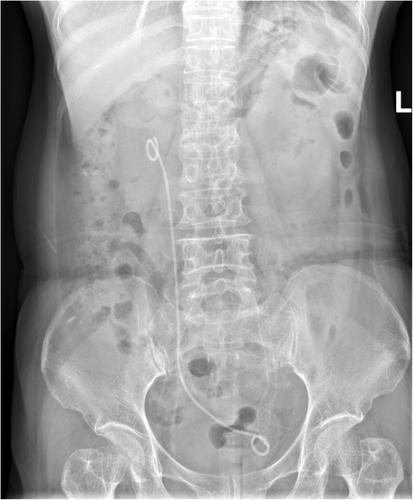

Following ureteroscopy, a guidewire was advanced under fluoroscopic guidance into the renal pelvis. The retrograde ureterography was performed to determine the location and length of the ureteral stricture. Dilation was performed using a ureteral balloon dilator, a flexible ureteroscope sheath, or a rigid ureteroscope. Subsequently, the Allium stent was deployed into the stricture segment and confirmed via fluoroscopic imaging.